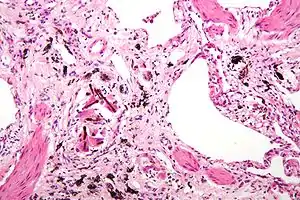

| عکاسی ریزنگاری of asbestosis showing the characteristic ferruginous bodies and marked interstitial fibrosis (or scarring). H&E stain. | |